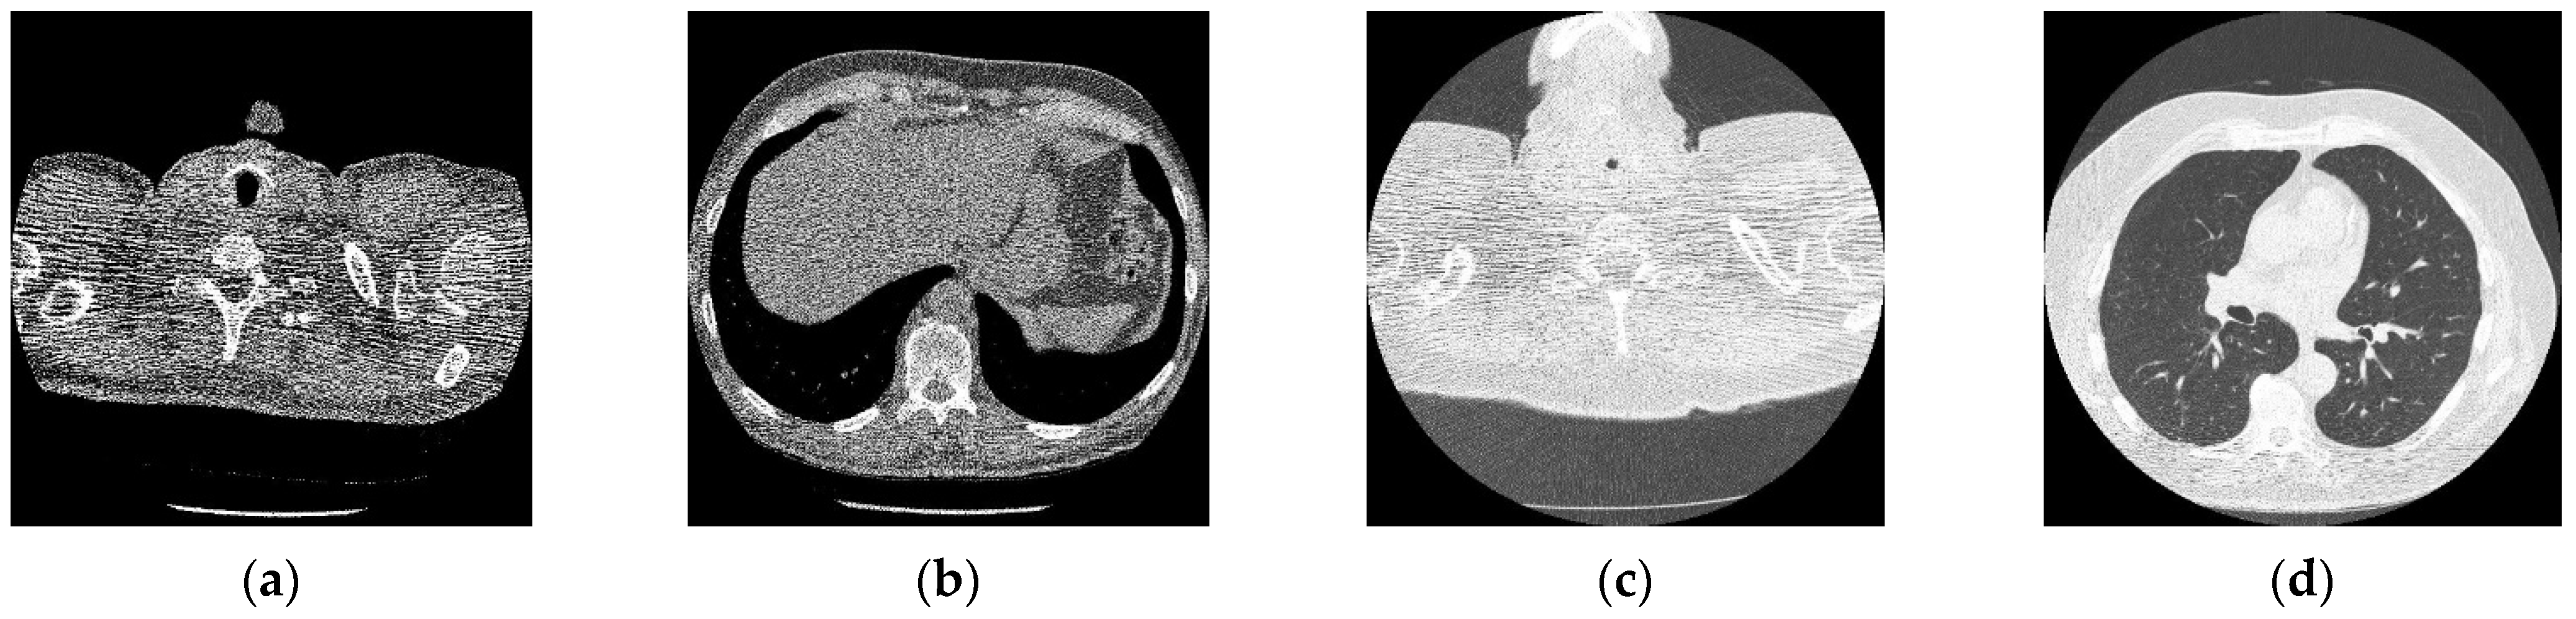

In this section, the experimental results of the proposed method over noisy CT images with their performance aspects are presented. All the experiments are performed on the standardized and simulated CT image data set with artificially introduced white Gaussian noise. Additionally, qualitative, quantitative, and graphical analysis is done to provide evidence for the efficacy of the proposed method. The reference CT image dataset is shown in Figure 2. The CT images are of [512 × 512] resolution size, which is used for consistency. This framework can work with dynamic image size, and performance commensurate to the available hardware. The image shown in Figure 2d refers to grayscale using built-in MATLAB functions before use.

Figure 2.

Online access database of original CT images [49]; (a) Reference CT1 image; (b) Reference CT2 image; (c) Reference CT3 image; (d) Reference CT4 image.